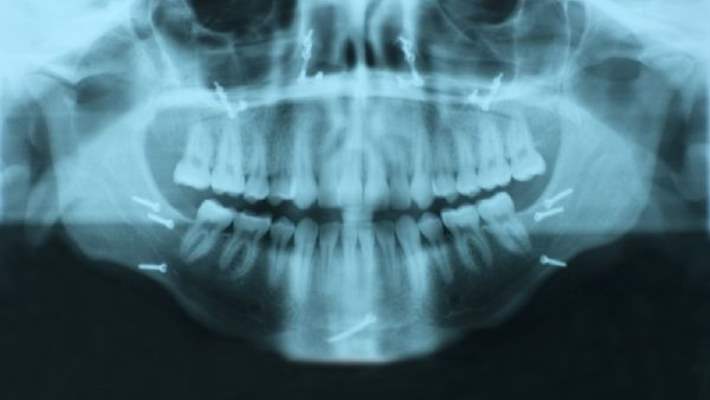

Çene kemiği yüzün alt kısmındaki en büyük ana kemiktir. Çene kemiğinin önemli bölgeleri, rami denilen yukarı bakan iki dal ile gövdeden oluşur (çene kıvrımını oluşturan yer). Erkeklerde çene kemiği kırılması kadınlara göre üç kat fazladır. 20 ila 29 yaşları arasında olanlar en fazla etkilenen gruptur.